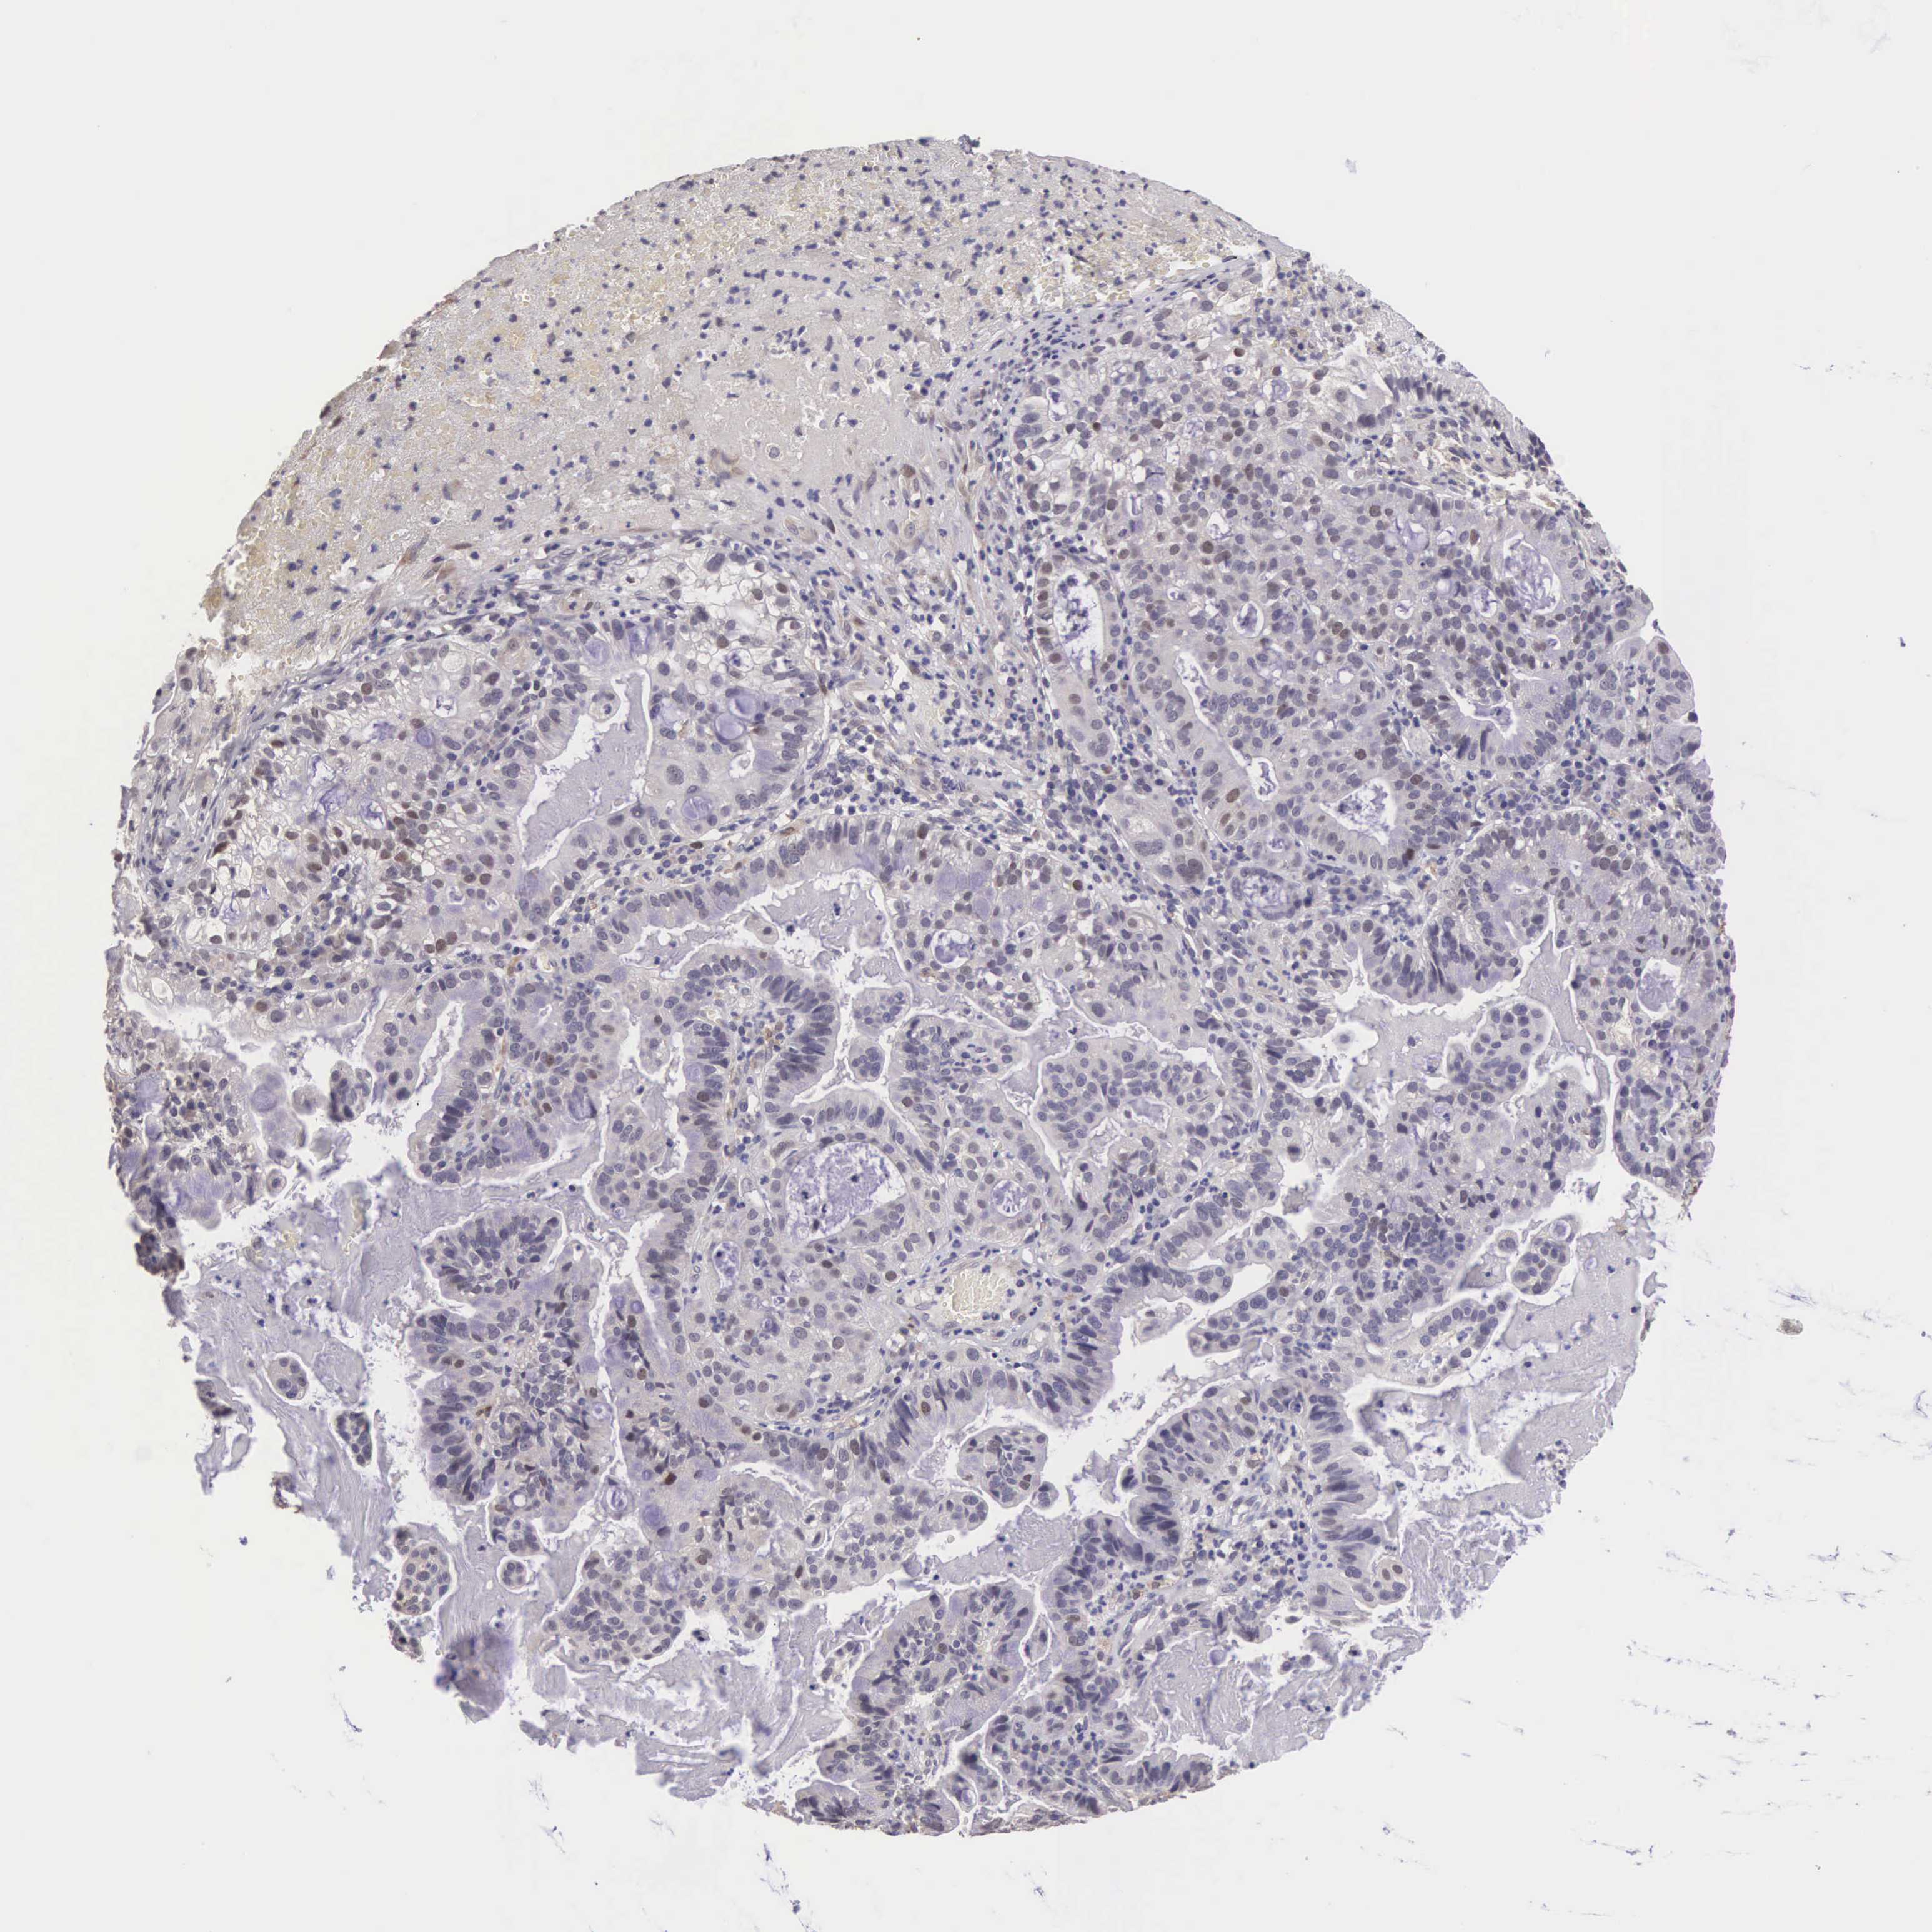

CERVICAL CANCER - Protein expressioni

A mouse-over function shows sample information and annotation data. Click on an image to view it in a full screen mode. Samples can be filtered based on level of antibody staining by selecting one or several of the following categories: high, medium, low and not detected. The assay and annotation is described here.

Note that samples used for immunohistochemistry by the Human Protein Atlas do not correspond to samples in the TCGA dataset.

Antibody stainingi

Antibody staining in the annotated cell types in the current human tissue is reported as not detected, low, medium, or high, based on conventional immunohistochemistry profiling in selected tissues. This score is based on the combination of the staining intensity and fraction of stained cells.

Each image is clickable and will lead to virtual microscopy that enables deeper exploration of all samples and also displays staining intensity scores, fraction scores and subcellular localization as well as patient and tissue information for each sample.

Antibody HPA000614

Antibody CAB009459

Staining

High

Medium

Low

Not detected

Intensity

Strong

Moderate

Weak

Negative

Quantity

>75%

75%-25%

<25%

None

Location

Nuclear

Cytoplasmic/membranous

Cytoplasmic/membranous,nuclear

Adenocarcinoma, NOS

Squamous cell carcinoma, NOS